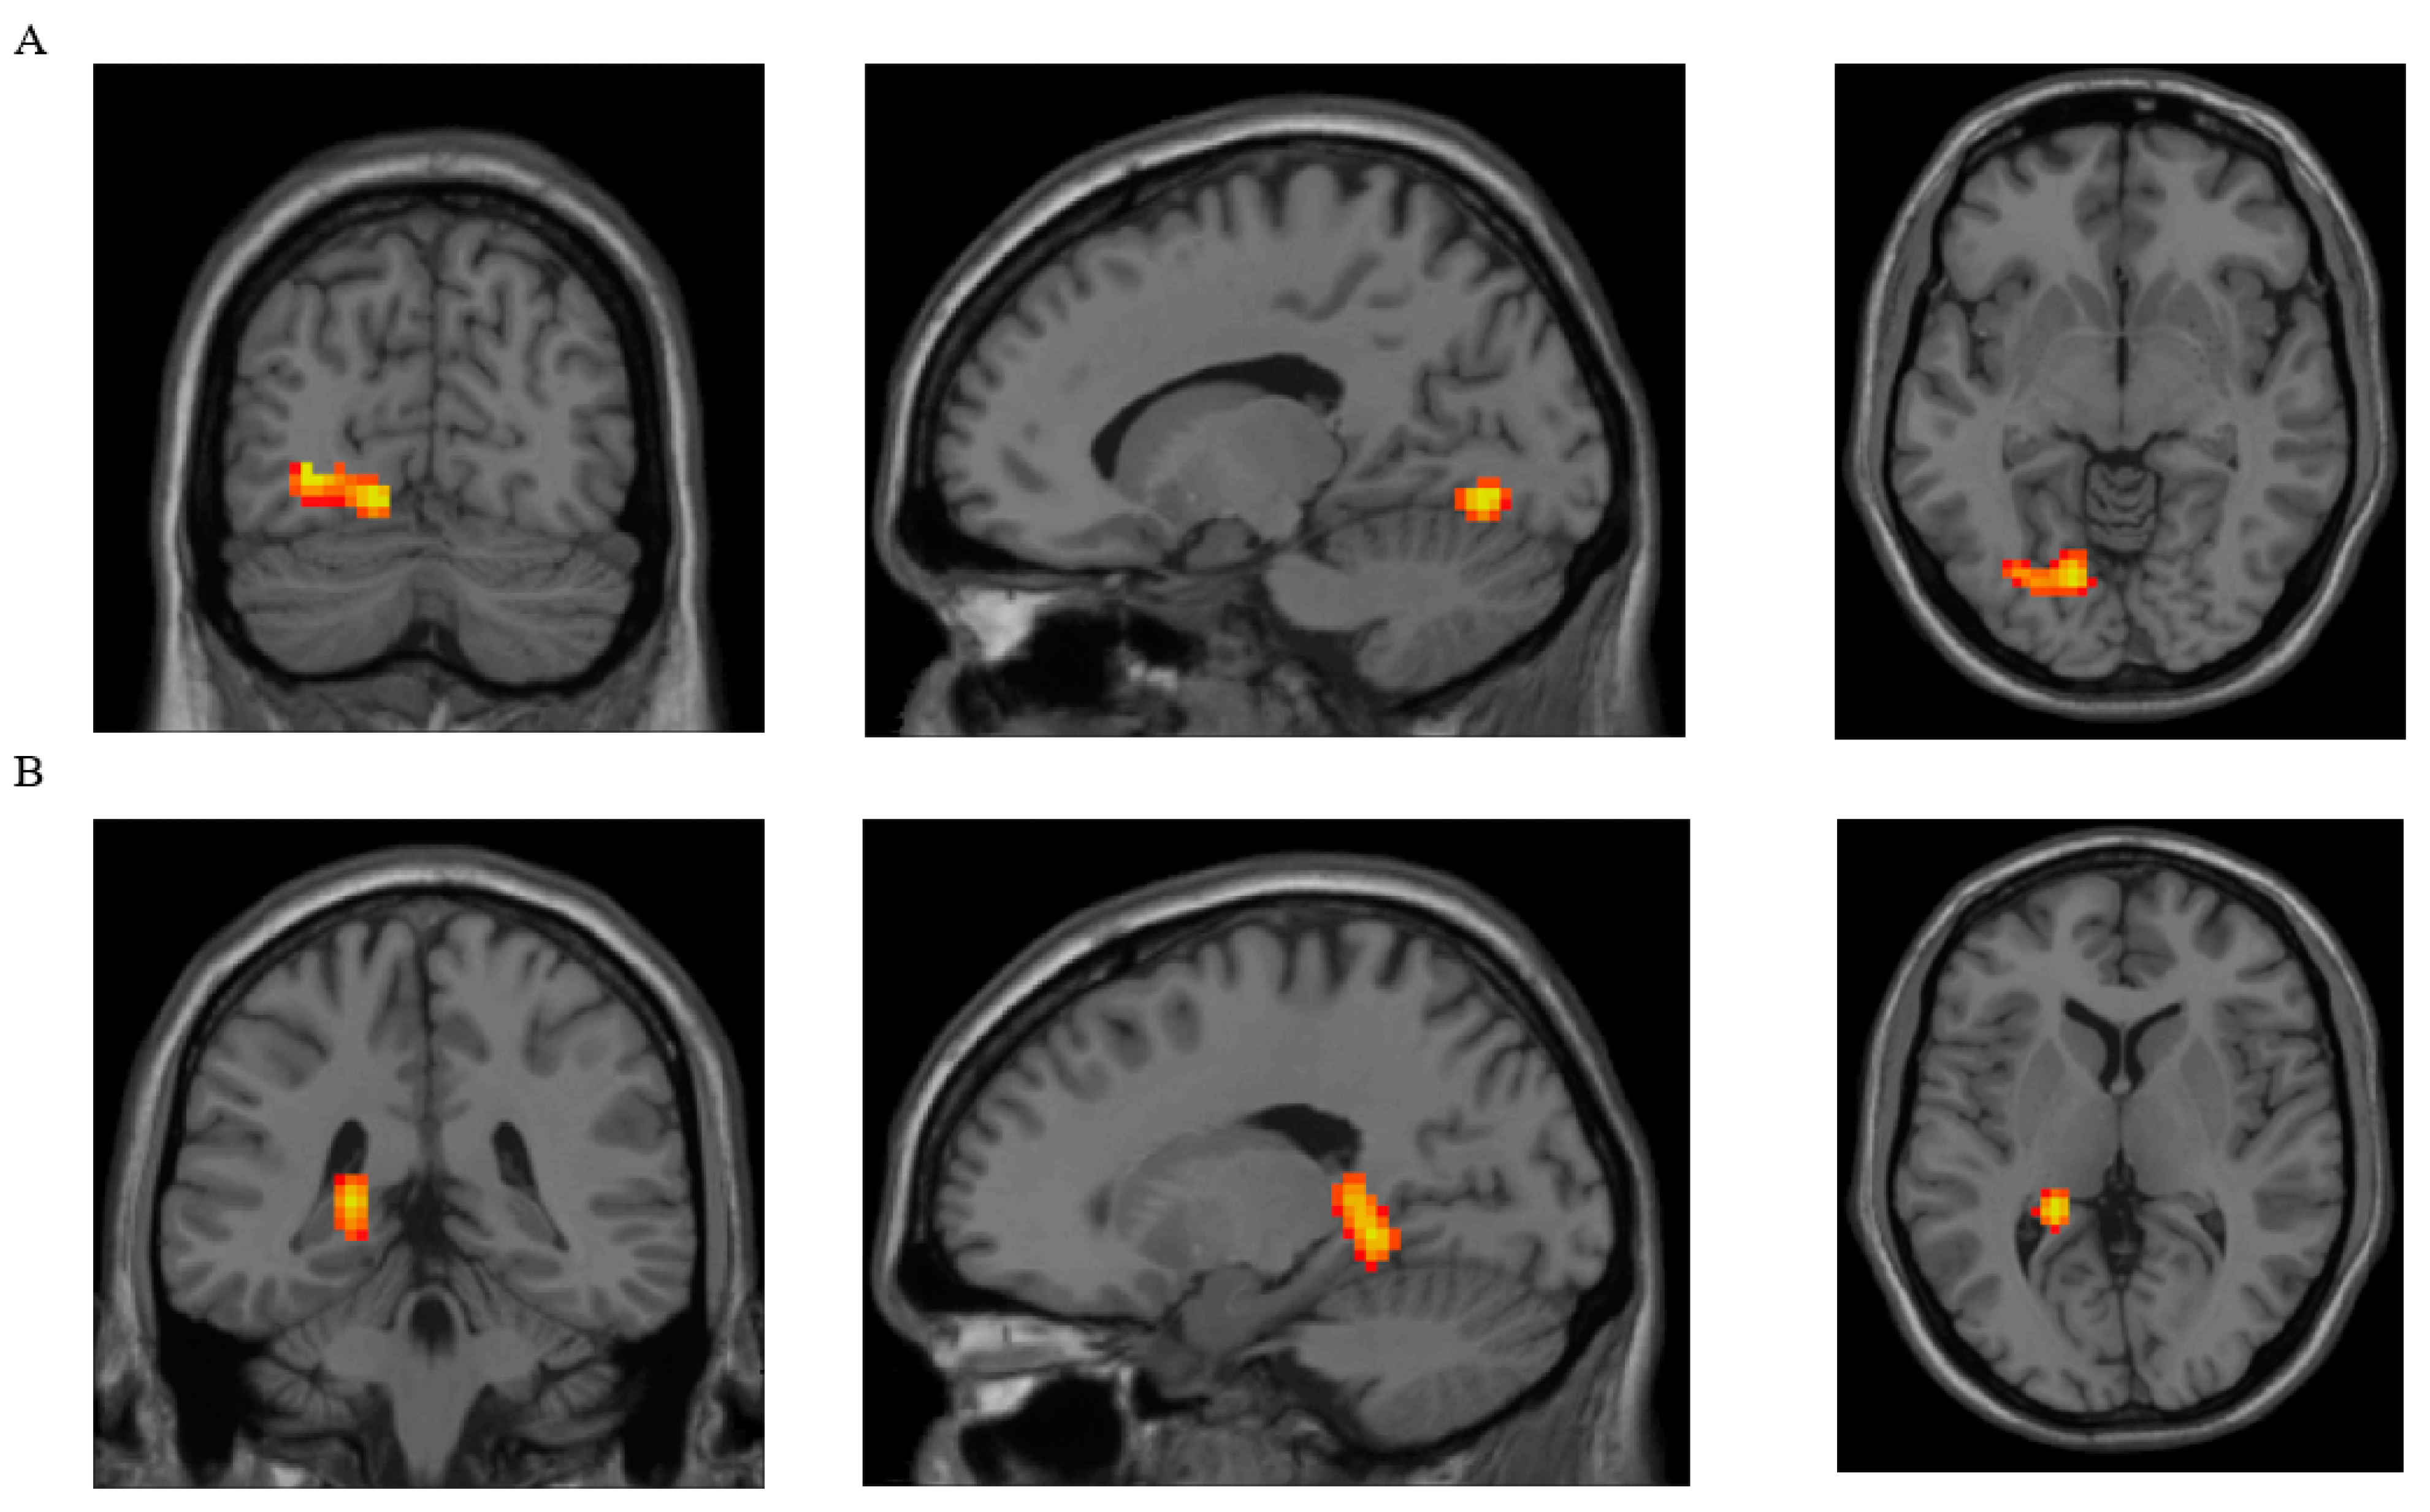

| Parameter | Brain Region with Clusters That Showed Significant Differences between Groups | Brodmann Area | Peak MNI Coordinates of the Cluster | Cluster Size (Voxels) | ||

|---|---|---|---|---|---|---|

| x | y | z | ||||

| DC | Lingual, L | 18 L | −15 | −72 | −6 | 102 |

| ReHo | Lingual, L | 37 L | −21 | −42 | −6 | 163 |